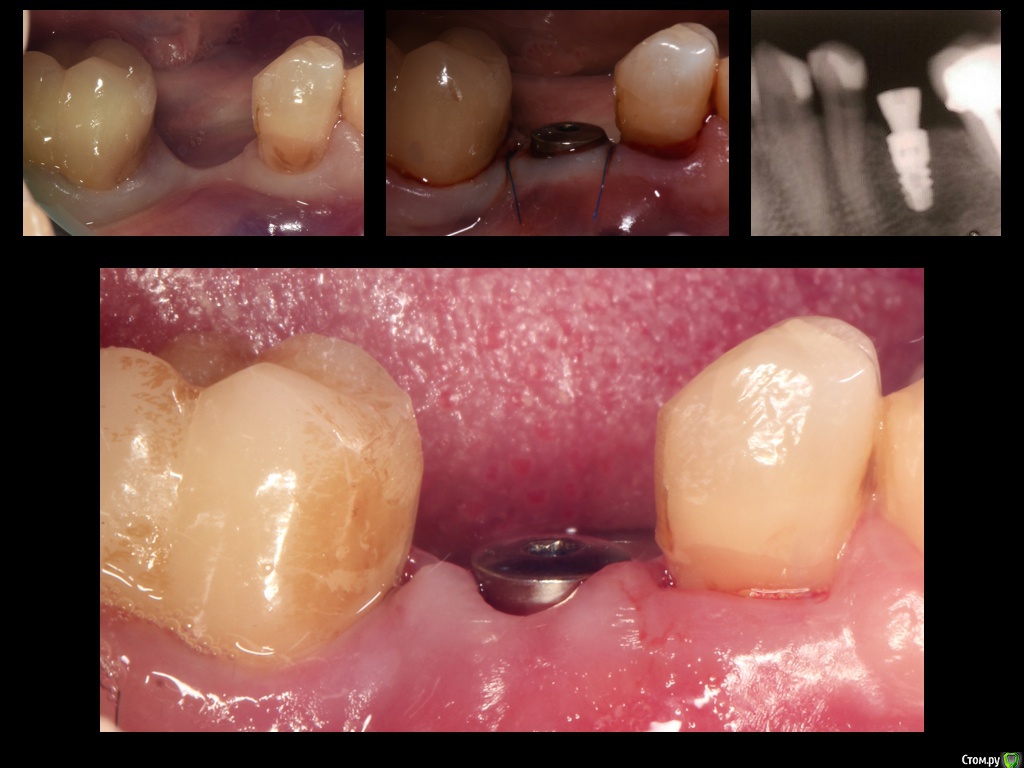

Фото после снятия швов через 1 неделю